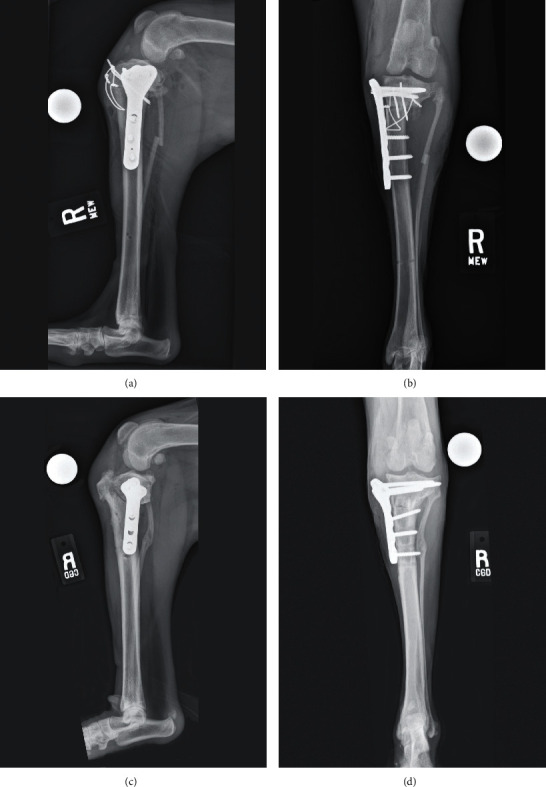

一只9个月大的混血狗因双侧胫骨近端畸形导致胫骨平台角过大和颅交叉韧带功能不全。右侧骨盆肢体的初始手术处理是通过颅骨闭合楔形骨切除术完成的。平台水平不高导致半月板撕伤,在胫骨平台水平截骨手术中得到解决。左侧骨盆肢体在一次手术中使用三维(3D)虚拟手术计划和定制的3D打印手术指南进行联合颅合楔形骨切除术和胫骨平台平切术。术后左胫骨的三维分析显示,手术结果的准确性在虚拟手术计划的2°以内。手术后,狗出现了短暂的II/IV级左内侧髌骨脱位,但最终实现了完全的功能恢复,并在手术后46个月积极参与左骨盆肢体的竞技敏捷性工作。

A 9-month-old mixed-breed dog was presented for bilateral proximal tibial deformity resulting in an excessive tibial plateau angle and cranial cruciate ligament insufficiency. Initial surgical management of the right pelvic limb was done by performing a cranial closing wedge ostectomy. Inadequate leveling of the plateau resulted in a postliminal meniscal tear which was addressed during a revision tibial plateau leveling osteotomy. The left pelvic limb was managed in a single-session surgery using three-dimensional (3D) virtual surgical planning and custom 3D-printed surgical guides to perform a combined cranial closing wedge ostectomy and tibial plateau leveling osteotomy. Postoperative 3D analysis of the left tibia revealed the accuracy of the surgical result within 2° of the virtual surgical plan. The dog developed a transient grade II/IV left medial patellar luxation following surgery but ultimately attained a full functional recovery and was actively engaged in competitive agility work 46 months following surgery on the left pelvic limb.